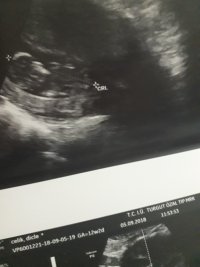

Dun malatyada verildi 12 +4 gunluk lutfen yorumlayin

nub çıkıntısının üzerinde imleç var cinsiyet anlaşılmıyor ilk sayfayı incelemenizi öneriyorum görselin kalitesi konu içinde yer alan görselle aynı olmalıdır.

Görsellerde nub çıkıntısı belli değil . Ultrasonu yapan doktor cinsiyeti hakkında bilgi vermiştir mutlaka ama şunu belirtmeden geçmeyeyim. Bu haftalarda cinsiyet tahmininde yanılma payı çok yüksek 17-19 ve 20 ci haftalarda bebeğin cinsiyetini net olarak öğrenebilirsiniz.